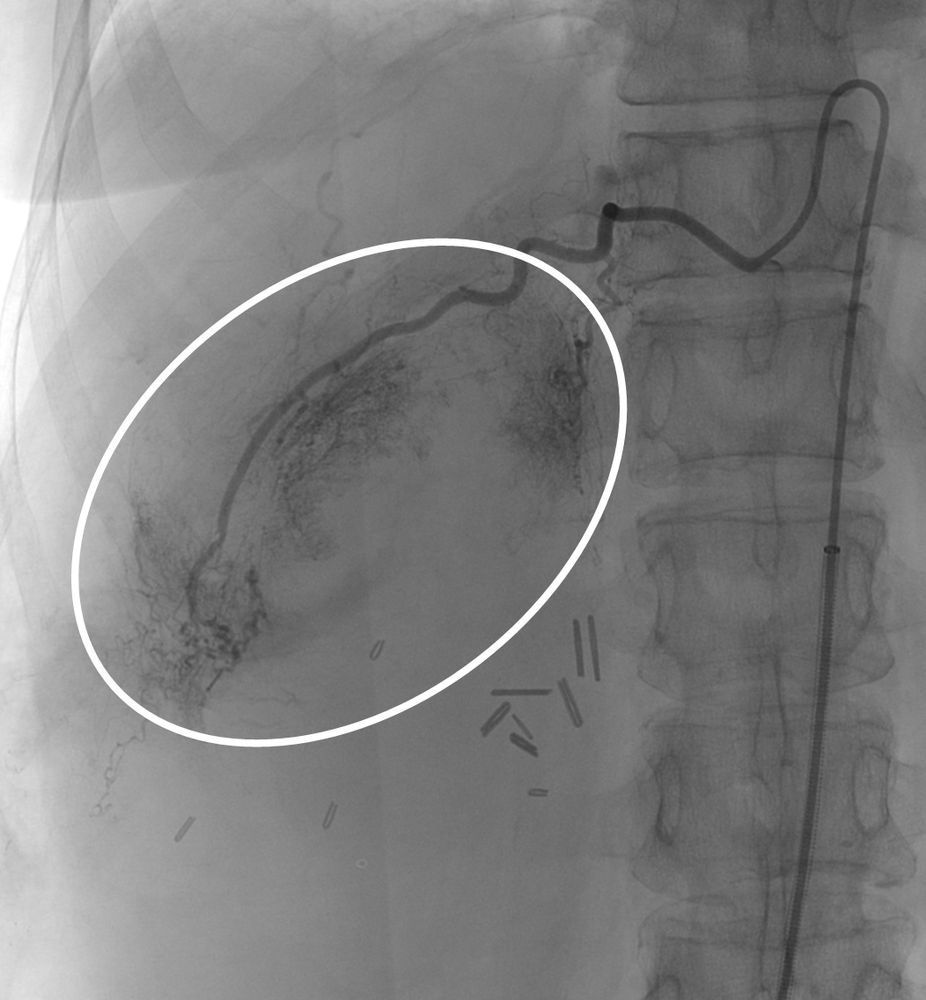

♦ Όγκους

Είτε προεγχειρητικά για την ελάττωση της αιμάτωσης του όγκου, είτε θεραπευτικά σε ορισμένες περιπτώσεις που δεν απαιτείται χειρουργείο ή υπάρχει αντενδειξη για χειρουργική αφαίρεση του όγκου.

Συνοπτικά υπό την καθοδήγηση του αγγειογράφου, αναγνωρίζεταιτο παθολογικό αγγείο-αγγεία και με ειδικούς καθετήρες και μικροκαθετήρες, διοχετεύονται εμβολικά υλικάόπως μικροσφαιρίδια ή coils, ώστε να αποφραχθεί ή να μειωθεί η παθολογική αγγείωση.